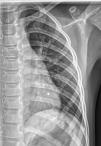

En radiografía de tórax realizada a nivel ambulatorio por cuadro respiratorio previo se objetiva imagen compatible con costilla bífida (fig. 1). Se realiza una tomografía computarizada de tórax (fig. 2) que confirma el diagnóstico, sin presentar patología adyacente. Se decide tratamiento conservador con seguimiento anual por Cirugía Pediátrica.